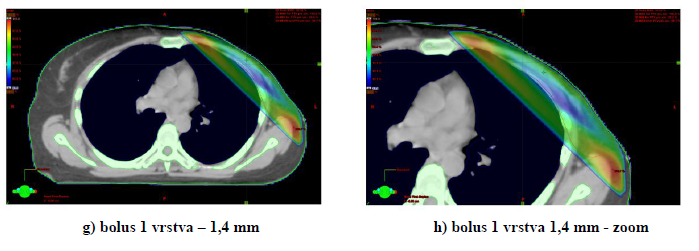

3) Distribuce dávky v oblasti hrudní stěny s bolusem a bez bolusu (TPS Eclipse).

K plánování ozáření s CT skeny používáme simulaci bolusu na hrudní stěně. Tloušťka bolusu ovlivní dávku na povrchu hrudní stěny.

Obr. 1: Distribuce izodoz na hrudní stěně po ablaci pro karcinom prsu